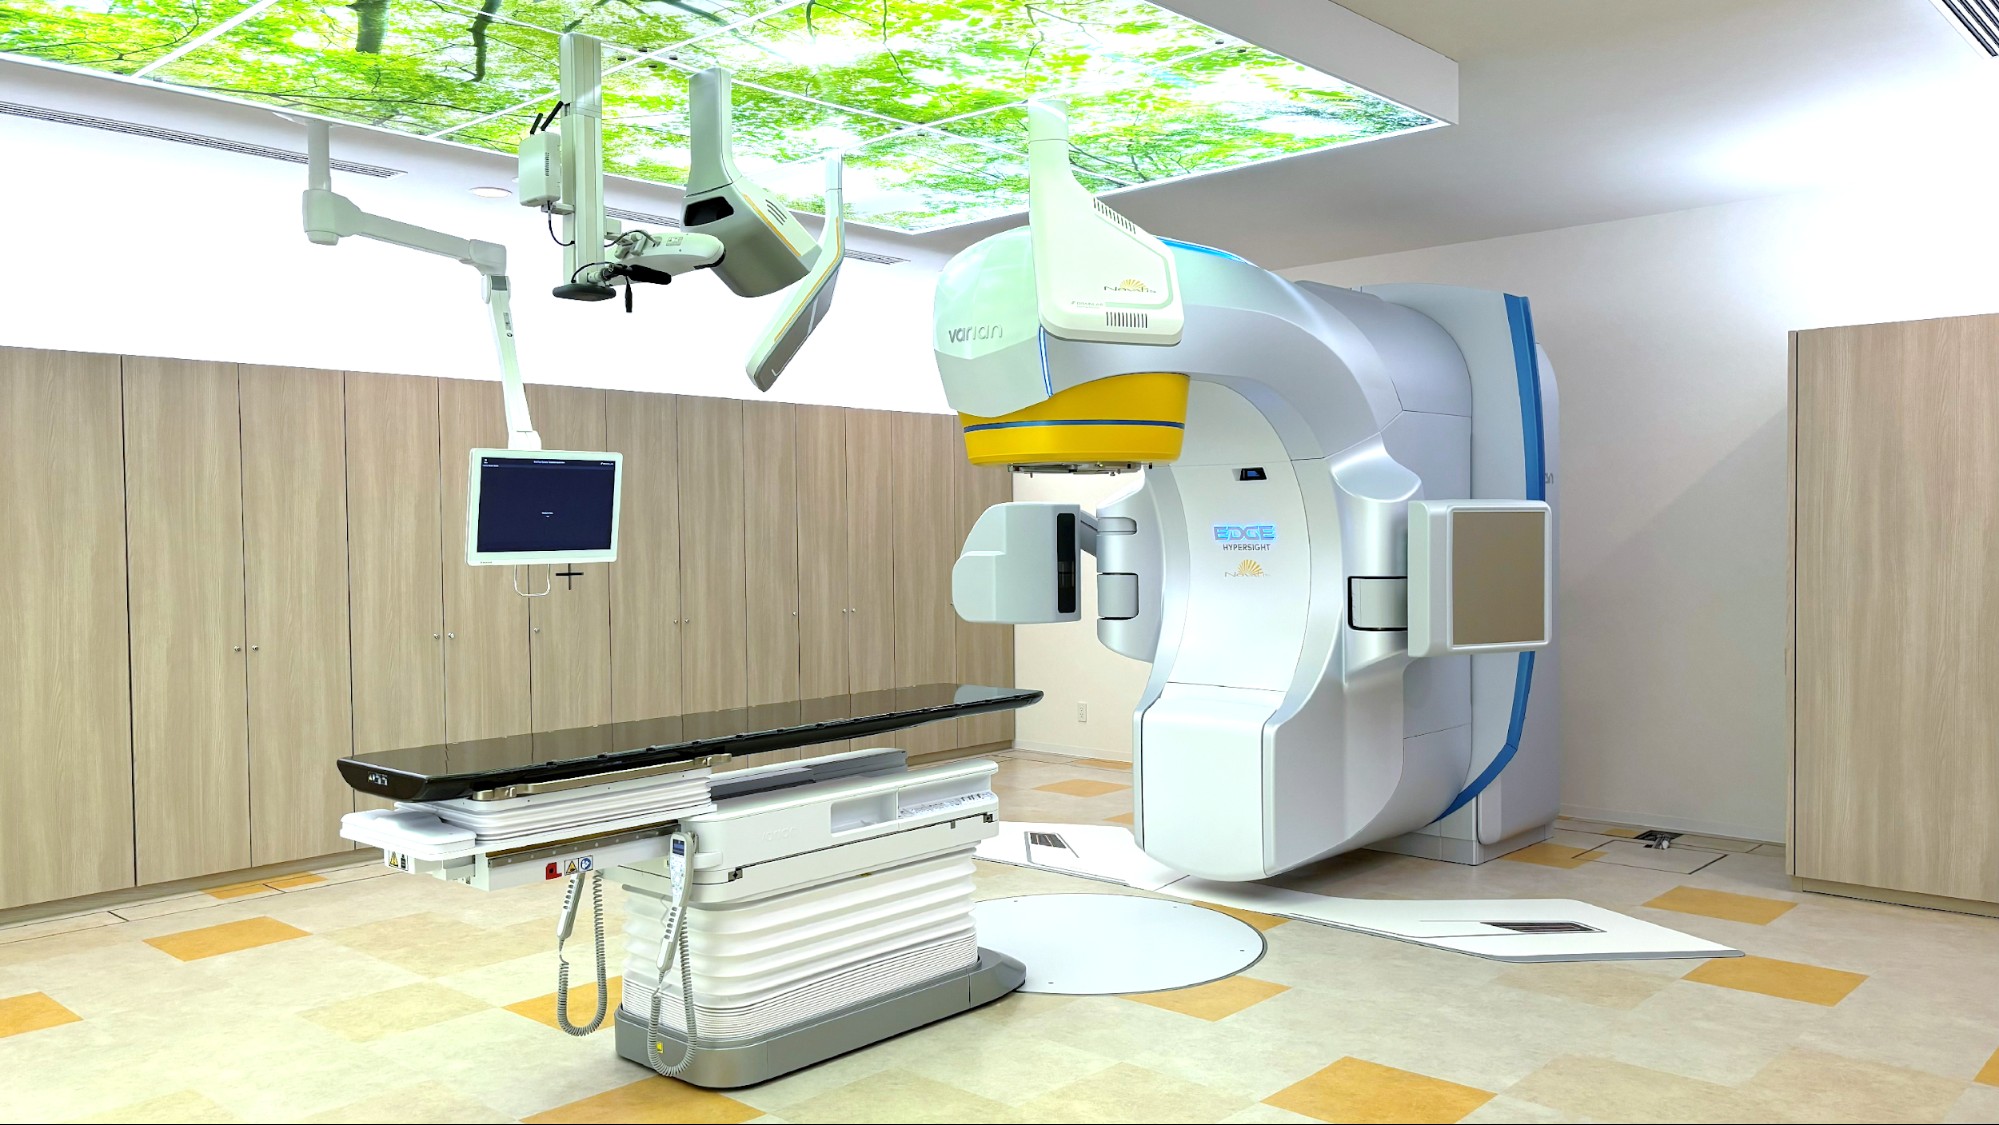

Novalis Edge(正式名称:Novalis powered by TrueBeam Edge HyperSight)は、バリアン社製の高精度リニアック「TrueBeam Edge HyperSight」と、ブレインラボ社製の定位放射線治療用画像誘導システム「Novalis Radiosurgery System」を組み合わせた放射線治療装置です。

TrueBeam Edge HyperSightとは

TrueBeam Edge HyperSight は、高精度な画像誘導や照射制御を活用し、病変に応じた放射線治療を行うための放射線治療装置(医療用リニアック)です。精密な治療計画に基づき、照射範囲や線量分布を適切に設定することで、周囲の正常組織への影響を可能な限り抑えた治療を目指します。

高精度リニアック本体(TrueBeam Edge)

高精度な放射線照射を行うための医療用直線加速器です。高い機械精度と高速な照射制御により、病変の形状に応じた線量分布の形成が可能です。

また、高線量率モードでは、6 MV X線で1,400 MU/分、10 MV X線で2,400 MU/分(通常照射モードでは600 MU/分)といった高速照射が可能であり、特に照射時間が長くなる定位放射線治療に有効です。

さらに、ロールやピッチ方向の補正が可能な PerfectPitch(6軸補正治療寝台)を搭載しており、患者さんの体位を高精度に補正することができます。